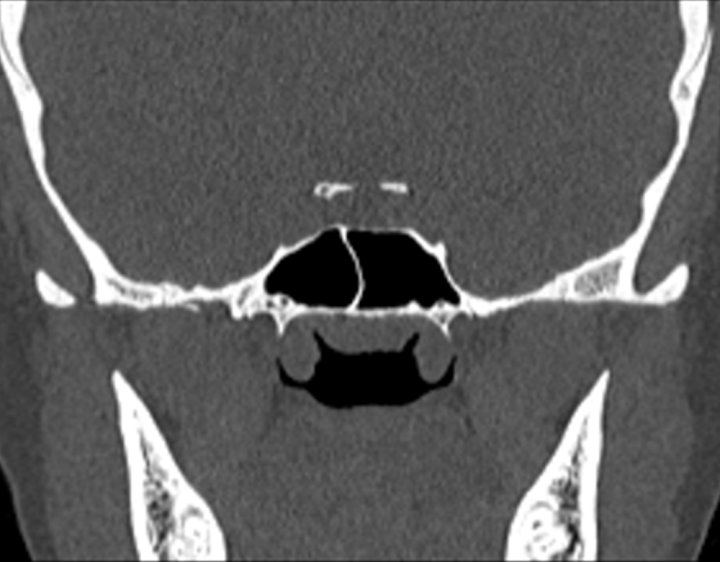

Click any image for labels.